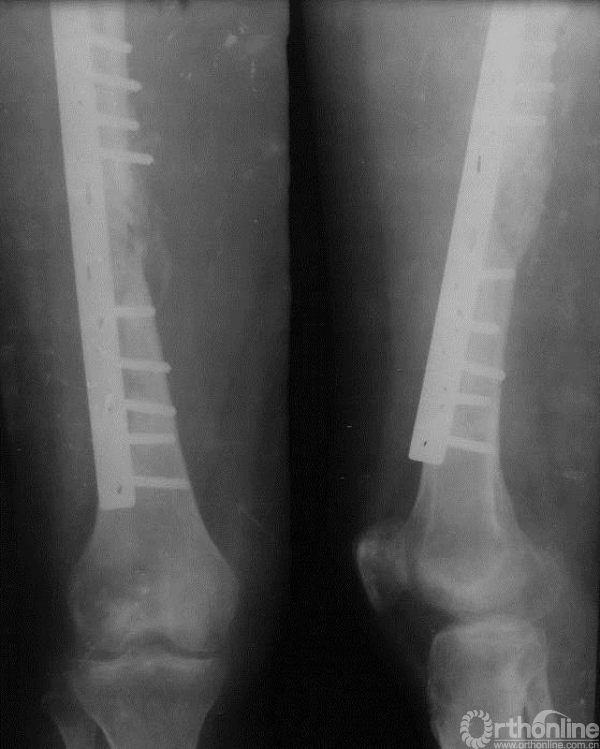

二次术前考虑一次手术时内固定方式仅为普通的髓内针,强度不足,且填充的骨水泥影响骨折愈合;此次未见明确局部复发,因此行髓内针及骨水泥取出、取髂骨植骨、钢板内固定术

图15-5 第二次术后X线平片正侧位

瘢痕组织及凝血块